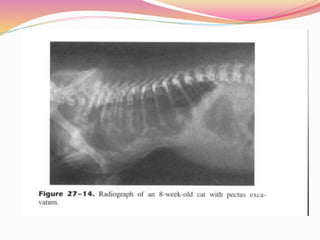

1. PECTUS EXCAVATUM

 Inward concave deformation of caudal sternum and

costal cartilages

 Retarded growth, dyspnoea, exercise intolerance,

vomiting, cyanosis

 Sx indicated if Cardio pulmonary effect is v severe

 Multiple chondrotomy, excision of malformed costal

cartilages, sternum struts, external splinting